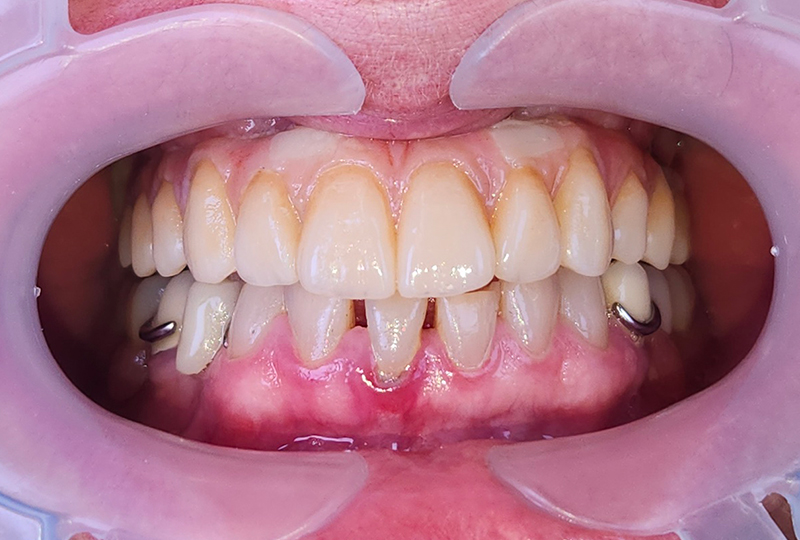

La barra, fresata in materiale metal-free su fresatore a 5 assi, sarà la trave portante della protesi, assemblata e incollata sul modello stampato (Figura 22). L’accoppiamento tra barra e impianti è affidato a TiBase Custom-Interface (IPD Dental Group / AbutmentCompatibili.com). I TiBase sono incollati con OT-Cem (Rhein83) sulla chiave in gesso di validazione finale per garantire la totale passività della struttura sia in laboratorio che sul paziente (Figure 23, 24). La consegna e la validazione finale avvengono con il serraggio della vite più distale e l’osservazione clinica della staticita’ struttura, seguita dal classico check radiologico mirato. (Figure 25, 26 e 27).

Consegna e RX controllo

Fig. 26, 27

Consegna e RX di controllo

Fig. 27